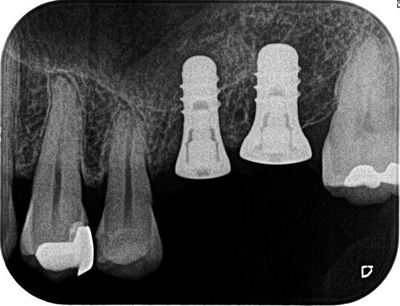

深度ゲージを挿入した状態でレントゲンを撮影します。

角度は想定どおりで安堵します。

オペ終了時のレントゲンです。

予定通りに進みホッとします。